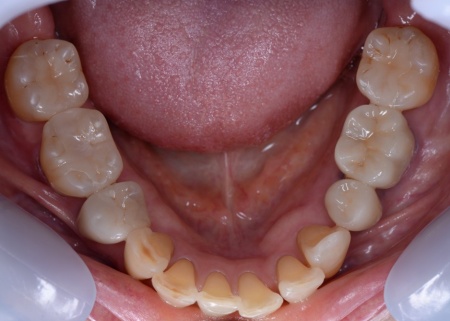

60代女性 すきっ歯が目立つ噛み合わせをワイヤー矯正とアライナー矯正の併用で改善した症例

まずはワイヤー矯正を行い、ある程度まで歯並びを整えます。

その後アライナー矯正に移行し、正しい歯並びになるよう調整を行いました。

最後に、噛み合わせや前歯の隙間が改善されたことを確認して、治療を終了しています。